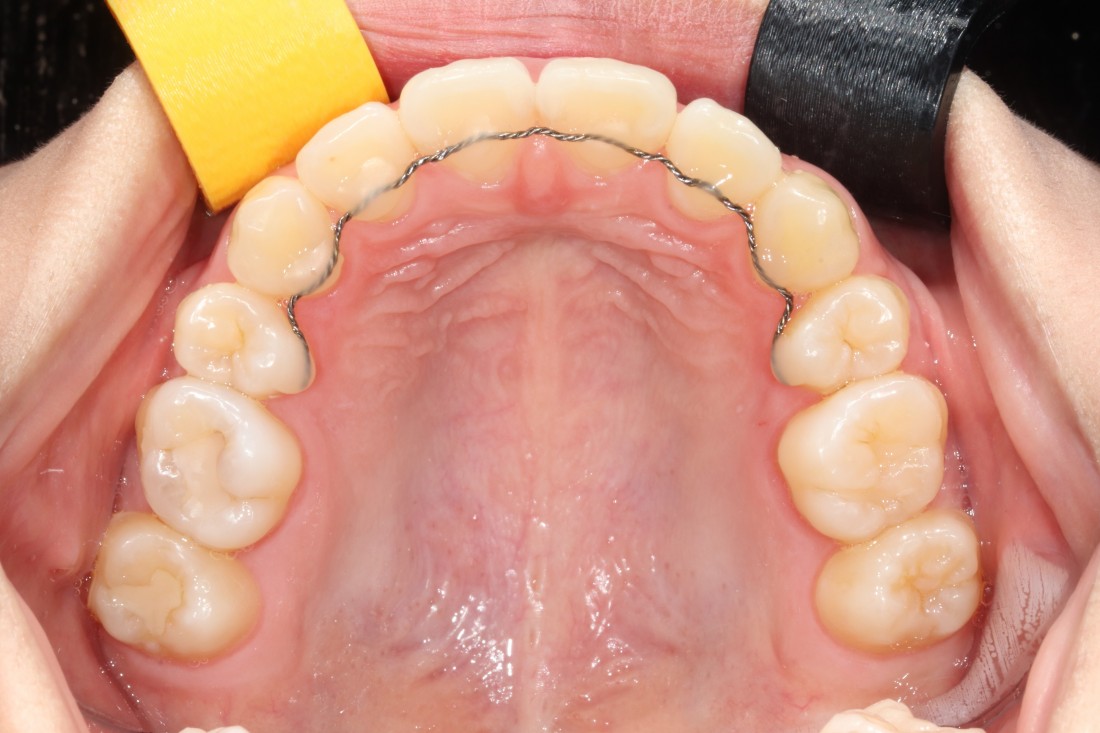

광주 성인 교정치과에서

충치치료와 교정진료를 동시에 받으신

성인 여성 환자분의 케이스입니다.

충치치료 전에는 은색 보철물이 있던 자리에

교정진료의 마무리와 동시에

치아색 보철물을 씌워서

치아교정 + 충치치료를 동시에 진행하였습니다.

광주 성인 치아교정의 경우

충치치료의 시기를 잘 판단하여

성공적인 진료를 완성할 수 있기 때문에

분과별 전문의가 협진하는

광주 성인 교정치과를 선택하시는 것이 좋습니다.